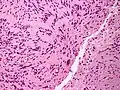

| Micrograph of a palisaded encapsulated neuroma | |

PEN is diagnosed by clinical recognition of the lesion and on subsequent histologic examination. Typically, the lesions are suspected to be schwannomas or neurofibromas clinically with PEN being an incidental finding on histology.[3]

PEN is typically diagnosed in patients between the ages of 40 and 60 years and occurs more frequently in females than males. The diagnosis of PEN may be difficult, even with confirmatory histology, due to its histological similarities with schwannomas and neurofibromas. It is imperative that the correct diagnosis is made the misdiagnosis of a neurofibroma may lead to unnecessary further investigation into associated systemic syndromes such as neurofibromatosis type 1 or multiple endocrine neoplasia syndrome.[3][4]